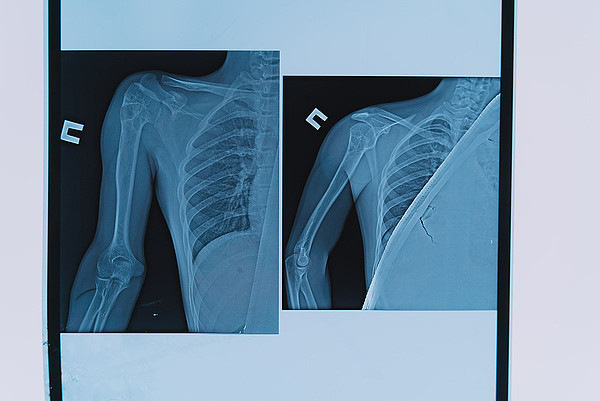

29112022-11.